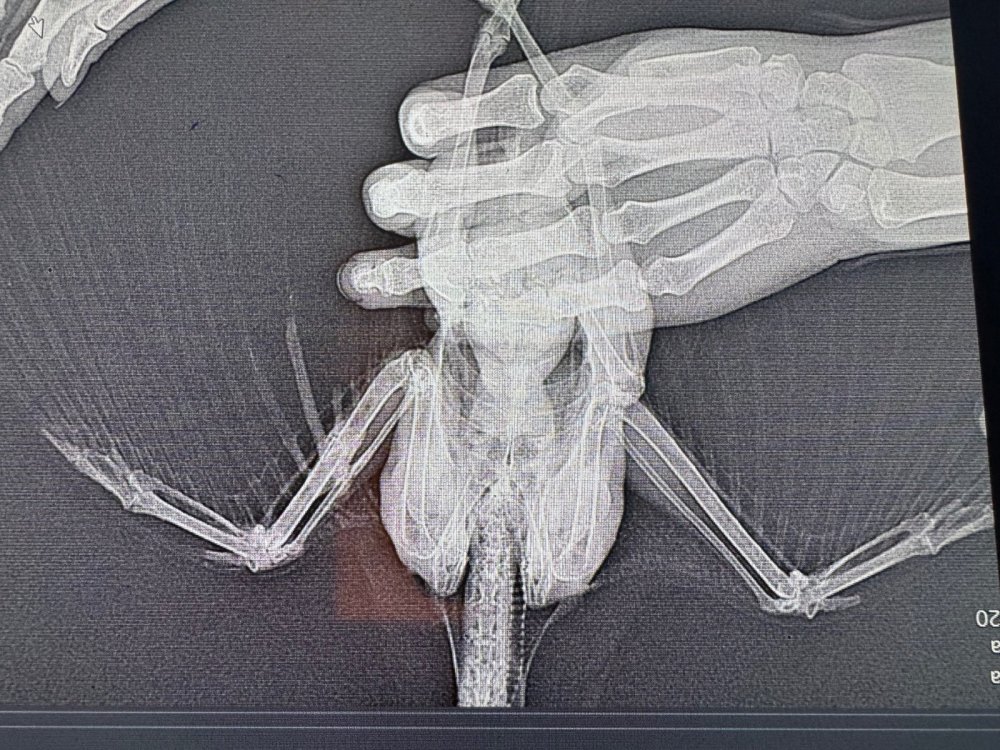

Здравствуйте! Подобрала молодого грача возле дома со сломанным крылом. В небольшом городе за лечение взялся лишь один ветеринар. Прооперировали 2 сентября опыта у меня нет, птицами никогда не интересовалась. После операции грачик хорошо питается (кормлю по гуглу - творог не жирный, мясо сырое, вареные куриные яйца; зофобас консервированный, гречка). Также даю минералы от зоомир общеукрепляющий. Активный, бесится, играется, танцует под гитару, но после операции меня немного побаивается, на руках больше не сидит как на первой фотографии. Сняли спицы 13 октября По поведению ничего не изменилось, кушает, пьет, бесится, по балкону до потолка взлетает. Но меня очень пугает, что крыло все еще висит и трясется. Последний рентген 23 октября Пожалуйста подскажите, что я могу сделать чтобы улучшить состояние крыла? Все ли хорошо по снимкам рентгена? Когда он начнет складывать крыло? Что я делаю не так? Из лечения никаких лекарств нам не назначали, только мумие. Я бы очень хотела оставить милашку у себя, но он уже бьется в окно, на улицу. Плюс мое место работы не позволяет заводить птиц, тк уезжаю на смену в другой город и не могу катать его с собой постоянно. Очень хотелось бы отпустить его к своим.